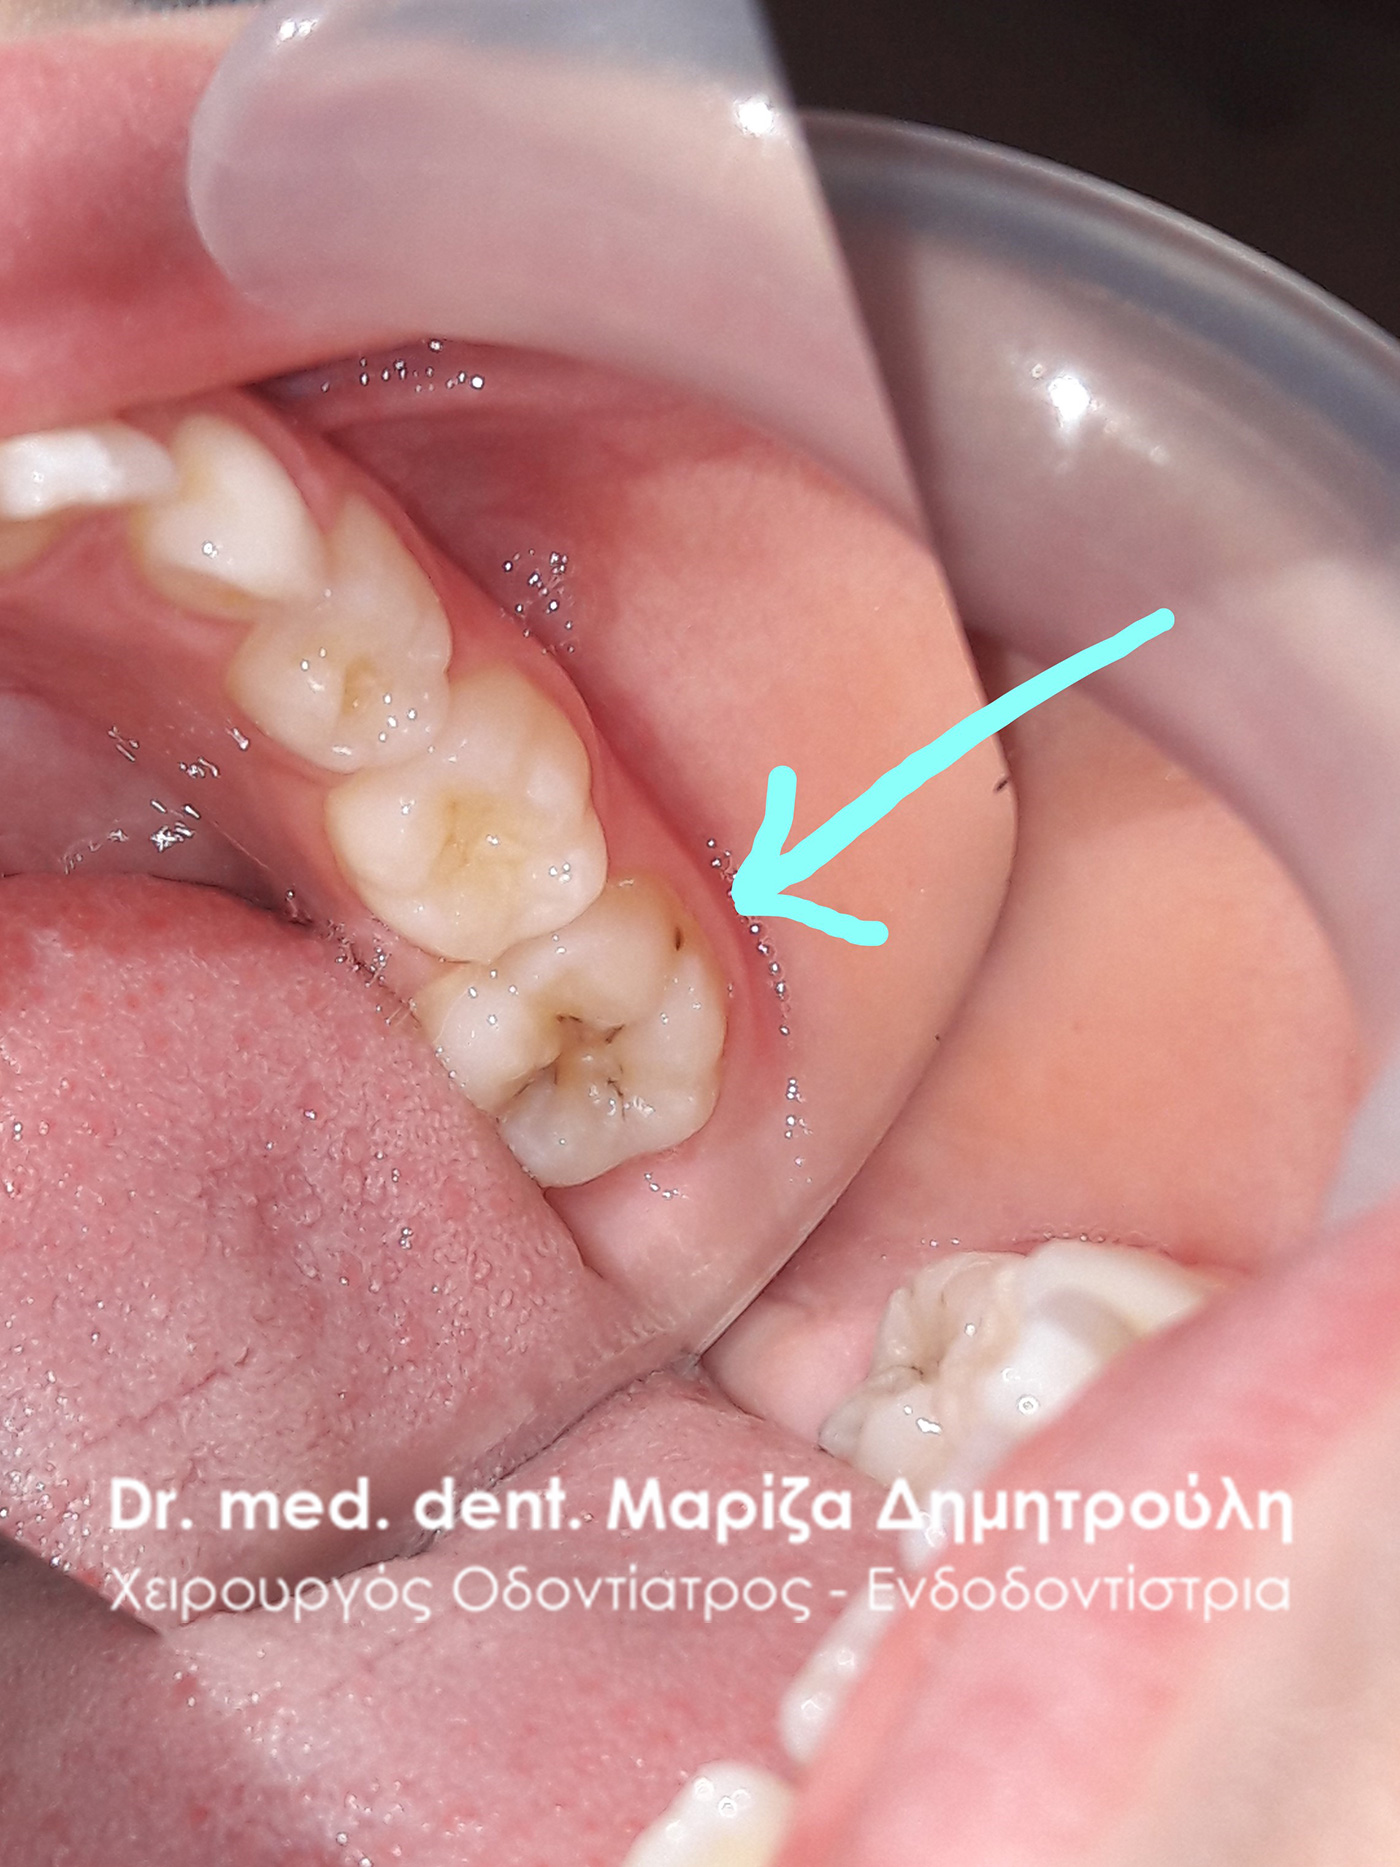

Dental filling of primary tooth

BEFORE

AFTER